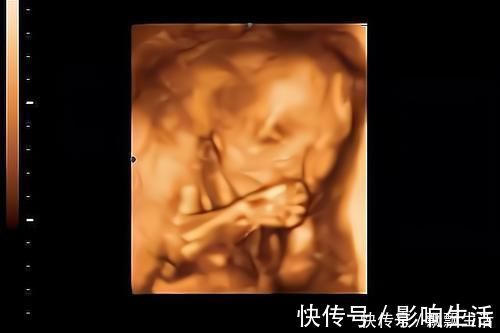

3.对孕妈的抚摸有反应

孕妈们可能会有这样的经历,当抚摸肚子,给宝宝做胎教、和宝宝说话时,胎宝宝可能很欢脱、很活跃。

不同性格的胎儿,对胎教时的表现也不一样。

性格偏安静、比较懒的宝宝,就算有“胎教刺激”时,也不一定会有反应。

而性格偏活泼好动的胎儿,当有“胎教刺激”时,会和妈妈“互动”的很欢,很愿意玩。